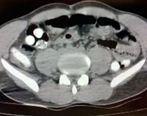

• بازداشت مسافر ایرانی با یک کیلو تریاک در معده در ترکیه +عکس معده مسافر ۰۴ تیر ۱۴۰۱

بازداشت مسافر ایرانی با یک کیلو تریاک در معده در ترکیه +عکس معده مسافر

یک مسافر ایرانی در شهر آغری ترکیه به اتهام حمل مواد مخدر دستگیر شد. مهران.ن یک کیلو و ۱۲۶ گرم مواد مخدر شامل تریاک را…